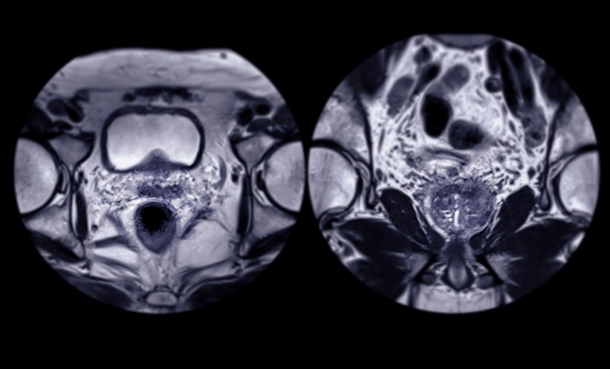

Immunohistochemical Biomarkers for Prognostic Stratification in Metastatic Prostate Cancer

New evidence shows PSA and Ki-67 tumour expression may help predict progression and guide treatment decisions in metastatic castration-sensitive prostate cancer.